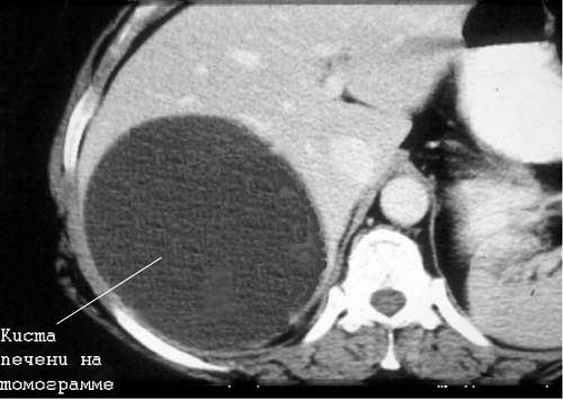

Киста печени

Чаще встречаются непаразитарные кисты. Учитывается возможность поликистозной болезни, а также солитарных и множественных истинных и ложных кист печени.

Большинство кист небольшие (диаметром 1-5 см), чаще встречаются у женщин. Значительная часть их имеет бессимптомное течение. У ряда больных отмечаются боли в правом подреберье, у одних — постоянные, у других — периодические. Существенную помощь оказывает использование УЗИ и КТ (или ЯМР), обладающие высокой разрешающей способностью. Необходимо учитывать возможность поликистоза печени.

Дифференциальная диагностика простых кист проводится также с паразитарными кистами печени (эхинококкоз). В пользу последних говорят положительные реакции с эхинококковым антигеном и Кацони, а также обнаружение в зоне опухолевидного образования обызвествлений, хотя и гемангиомы изредка могут обызвествляться.

Лечение кисты печени

Часть непарзитарных кист печени также подлежит оперативному лечению в связи с реальной возможностью их разрыва, инфицирования и кровоизлияния в просвет кисты. Кроме того, быстро растущие крупные кисты приводят к нарушению функций печени вследствие атрофии и замещения печеночной паренхимы кистозным образованием. Среди операций наиболее часто используют резекцию печени, перицистэктомию и вылущивание кисты.

В последние годы широкое распространение получили транспариетальные пункции кист под контролем УЗИ или КТ. После аспирации содержимого в просвет кисты вводят 96*раствор этилового спирта для склерозирования внутренней оболочки кисты. Эта операция эффектина приразмере кисты до 5 см. Если нет эффекта от данных способов лечения или киста имеет больший размер, показана операция — лапароскопическое иссечение участка кисты с последующей деэпителизацией внутренней оболочки кисты аргонусиленной плазмой или расфокусированным лучом лазера. Аналогичная тактика используется и при поликистозе печени. При осложненном поликистозе печени (нагноение, кровотечение, озлокачествление, сдавление крупными кистами желчных путей, воротной или полой вены) показано оперативное лечение. Обычно выполняют фенестрацию (вскрытие выступающих над поверхностью печени кист) с последующей деэпителизацией внутренней оболочки кисты.